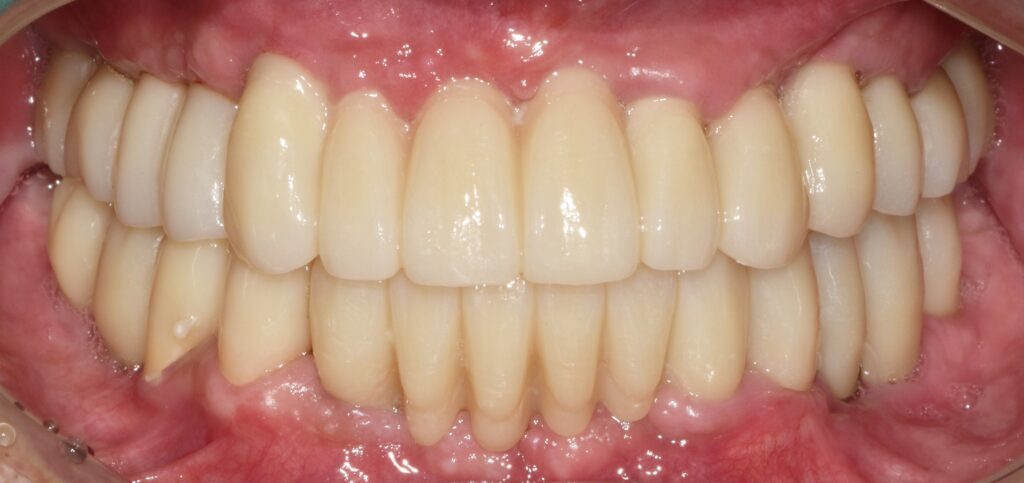

수술 및 보철 과정까지 완료

임플란트 수술과 보철까지 완료된 모습입니다.

환자분께서는 치료 전에는 틀니 사용으로 인한 불편함과 잇몸 통증,

식사 시의 제한 등으로 인해 일상생활에 어려움을 많이 느끼셨다고 합니다.

치료가 완료된 이후에는 식사나 발음, 구강 위생 관리 등 여러 면에서 개선을 체감하시며,

“이제야 마음 편히 식사를 할 수 있게 되었다”라고 이야기해 주셨습니다.

(해당 내용은 환자 개인의 치료 후기를 기반으로 하며, 치료 결과는 개인마다 다를 수 있습니다.)